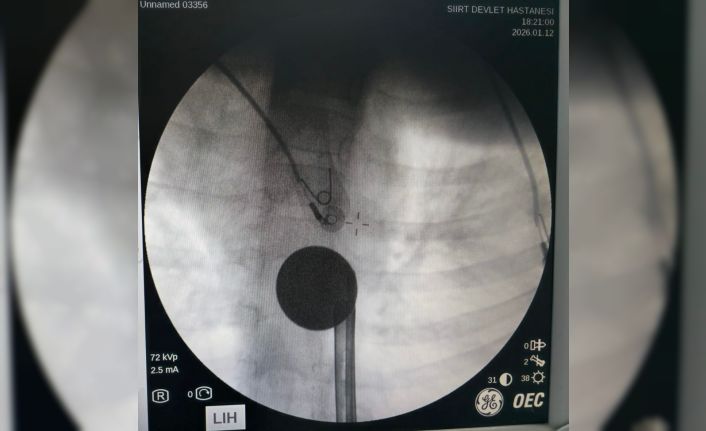

Yabancı cisim yutma şikayetiyle ailesi tarafından Siirt Eğitim ve Araştırma Hastanesine getirilen 8 yaşındaki Y.K., yapılan ilk değerlendirme ve görüntüleme tetkiklerinin ardından ilgili branşlarca operasyona alındı. Y.K.’nın yemek borusuna kadar ilerlediği tespit edilen madeni para, gastroenteroloji uzmanı Dr. Yaren Dirik ve kulak burun boğaz hekimi Yasin Gökçınar tarafından müdahale edilerek çıkartıldı. Operasyonun ardından bir süre gözlem altında tutulan Y.K., tedavisinin tamamlanmasıyla taburcu edildi.

Siirt Eğitim ve Araştırma Hastanesi Başhekim Yardımcısı Uzman Dr. Burak Özkan, çocuk hastalarda yabancı cisim yutma vakalarının ciddi riskler oluşturabileceğini söyledi. Uzm. Dr. Özkan, "Hastanemize başvuran 8 yaşındaki hastamızın yemek borusuna kaçan madeni para, gastroenteroloji ve KBB ekiplerimizin koordineli ve titiz çalışmasıyla herhangi bir komplikasyona yol açmadan başarılı bir şekilde çıkarılmıştır. Operasyon süreci sorunsuz geçmiş olup hastamızın genel durumu iyidir" dedi.